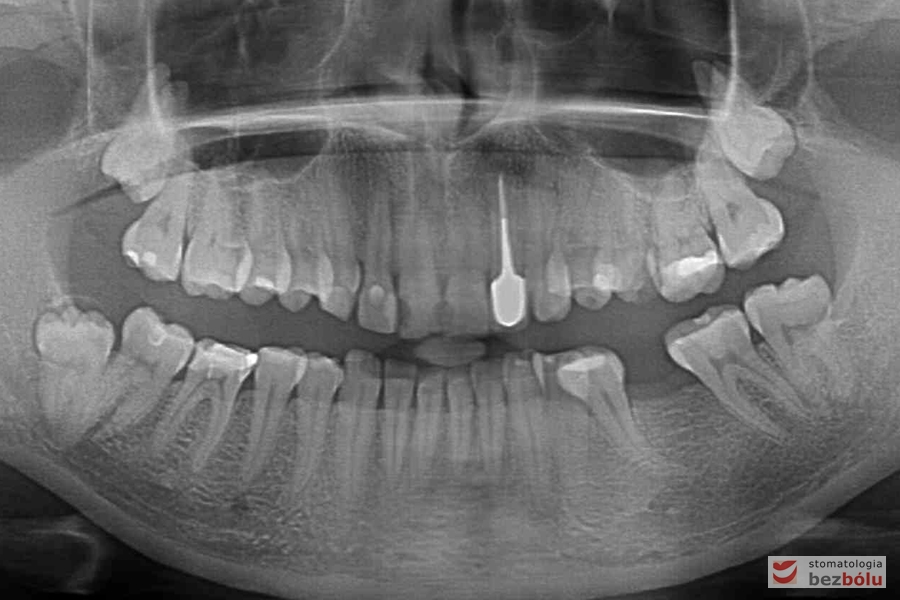

Diagnostyka pantomograficzna - brak pierwszego trzonowca lewego w żuchwie

Diagnostyka pantomograficzna – brak pierwszego trzonowca lewego w żuchwie